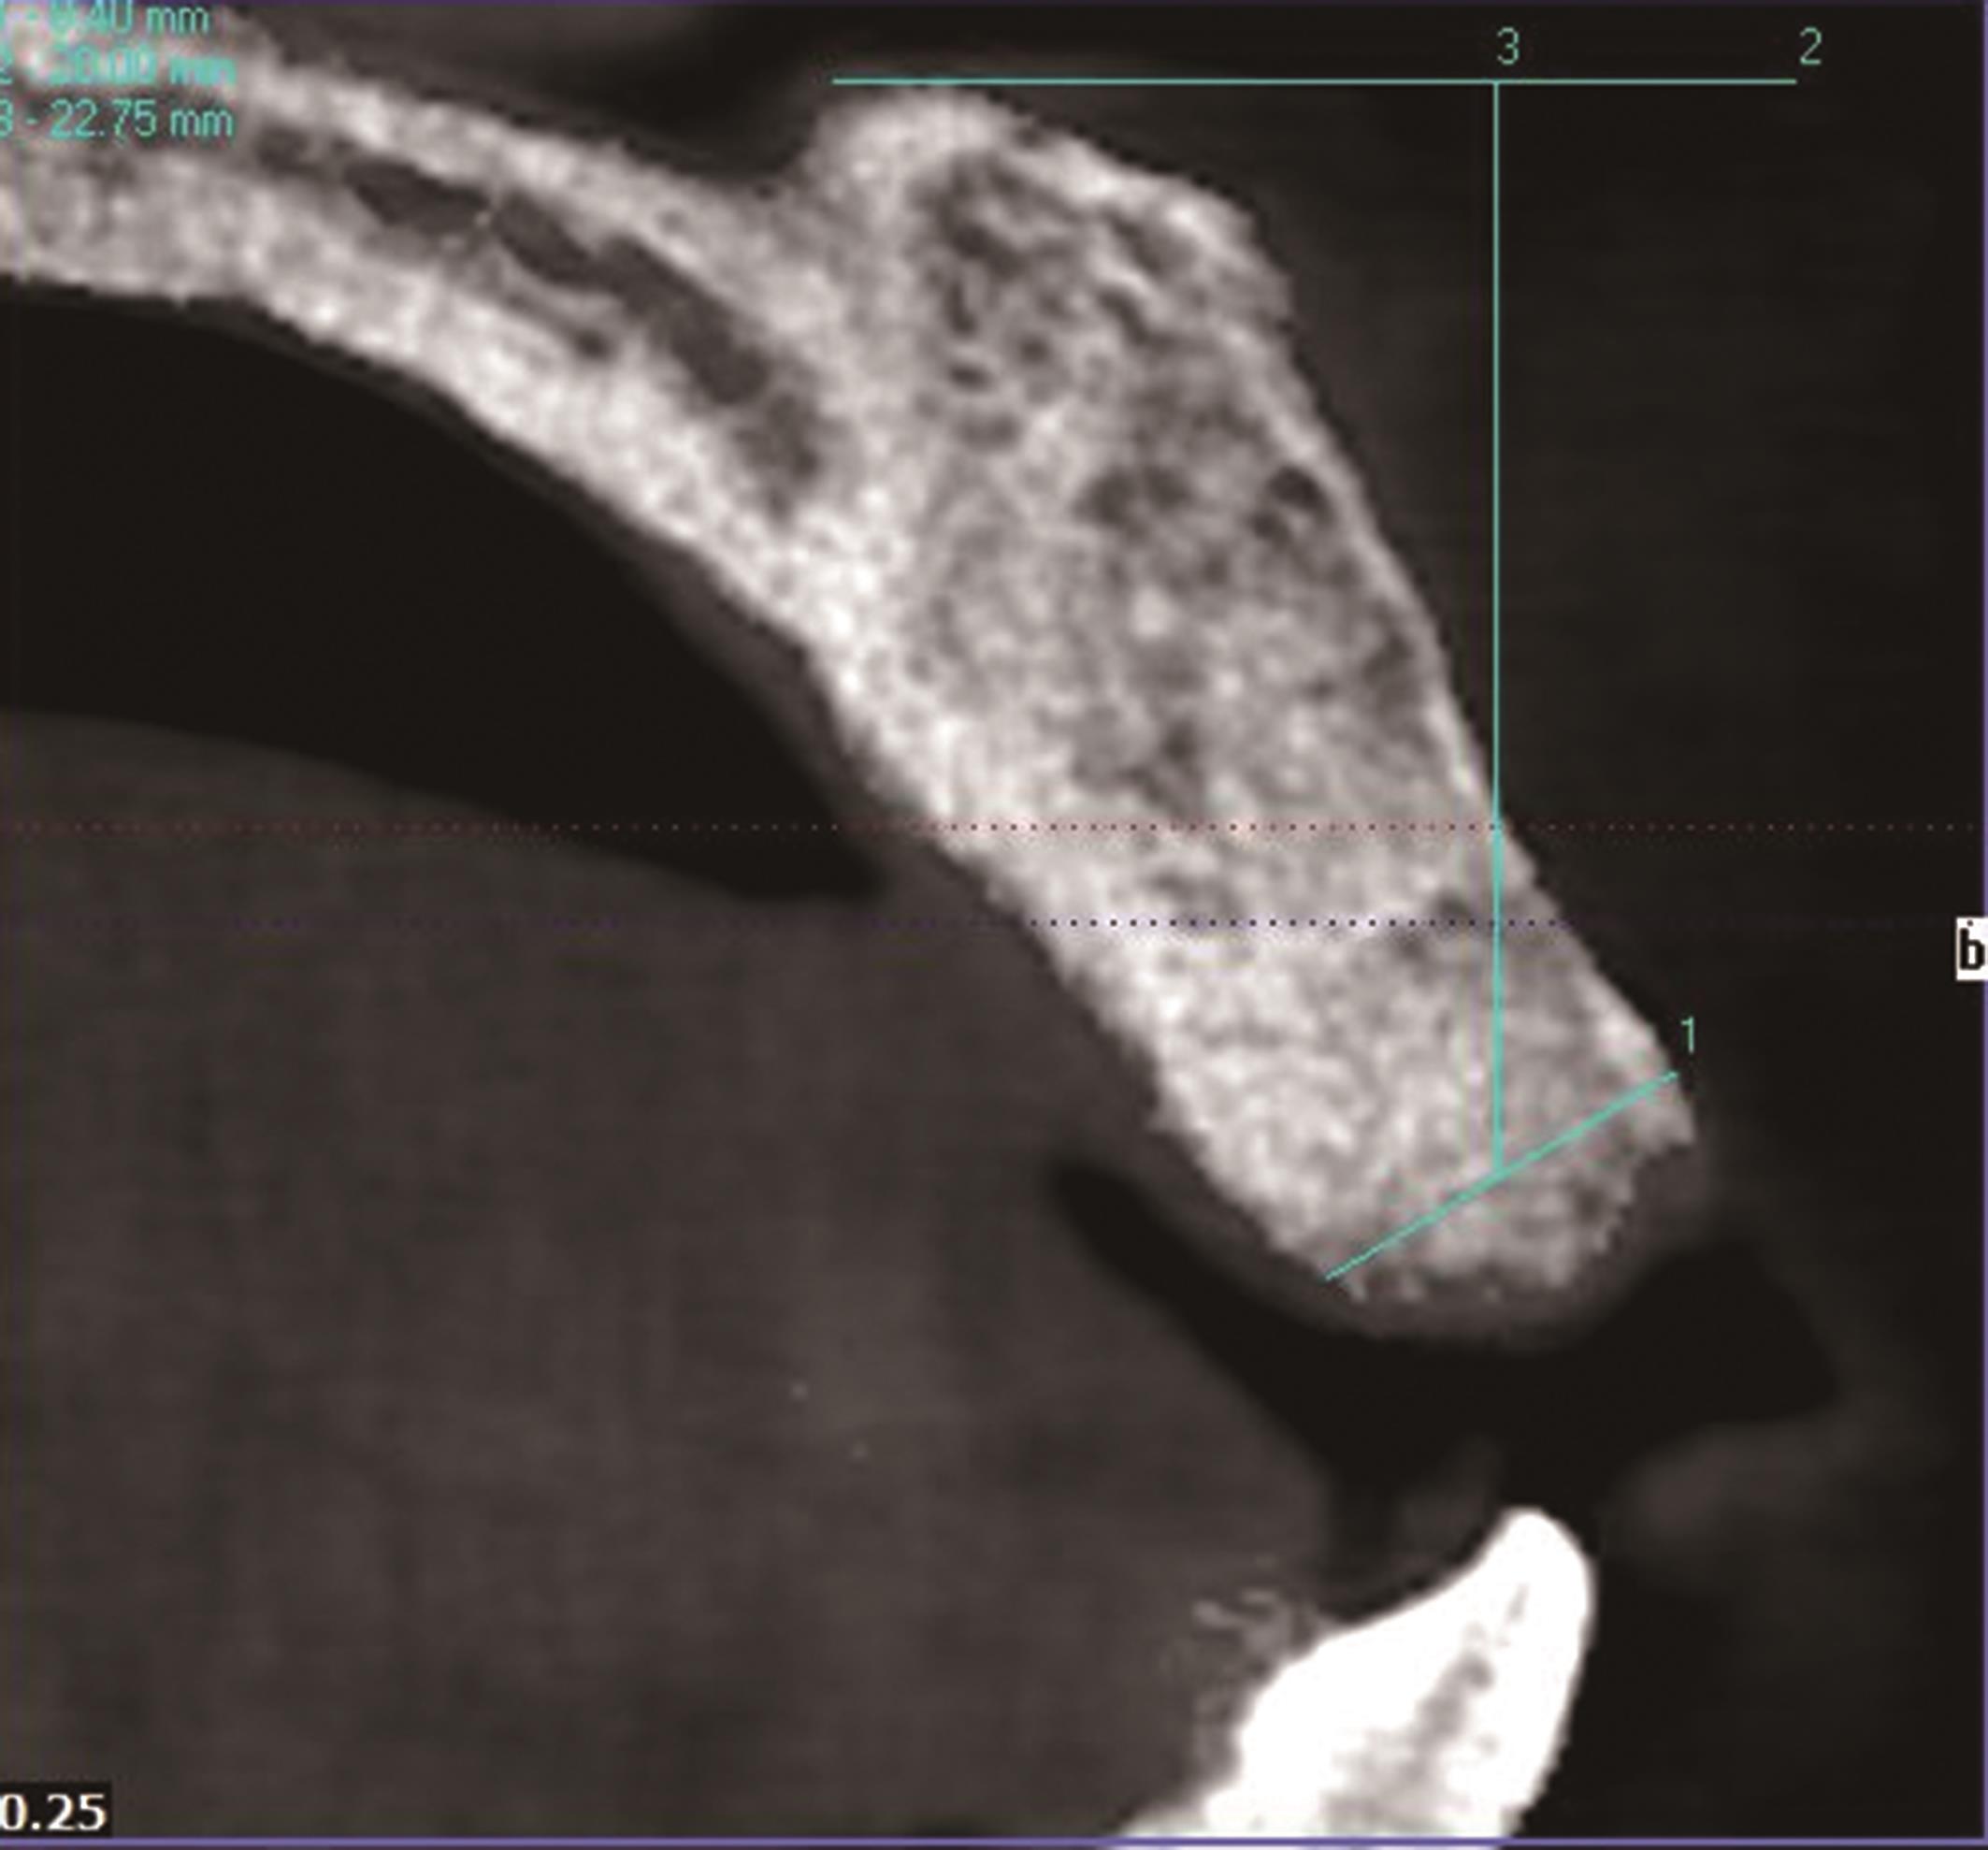

目的 比较浓缩生长因子(CGF)膜和Bio-Gide®胶原膜,分别与Bio-Oss®黏性骨联合用于上前牙牙槽嵴保存术(ARP)的临床效果。 方法 选取30例上前牙拔除后需要行ARP的患者,随机分为Bio-Gide组和CGF组。2组均在拔牙窝内严密充填Bio-Oss®黏性骨。Bio-Gide组用Bio-Gide®胶原膜覆盖于Bio-Oss®黏性骨上缘并封闭拔牙窝,CGF组用CGF膜覆盖并封闭拔牙窝。对比2组术后10 d软组织愈合情况,术后即刻及6个月牙槽嵴骨宽度及高度变化,以及术后6个月医患满意度。 结果 术后6个月,2组牙槽嵴骨宽度及高度变化差异无统计学意义(P>0.05)。但CGF组术后软组织愈合情况及医患满意度方面表现更优,差异有统计学意义(P<0.05)。 结论 与Bio-Gide®胶原膜相比,CGF膜与Bio-Oss®黏性骨联合应用可使上前牙ARP术后软组织愈合更好、医患满意度更高。

Objective To compare the clinical effects of concentrated growth factor (CGF) membrane and Bio-Gide ® collagen membrane, combined with Bio-Oss ® sticky bone respectively in alveolar ridge preservation (ARP) of maxillary anterior teeth. Methods Thirty patients who needed alveolar ridge preservation after maxillary anterior tooth extraction were selected and randomly assigned to the Bio-Gide group and the CGF group. In both groups, the extraction sockets were tightly filled with the Bio-Oss® sticky bone. In the Bio-Gide group used Bio-Gide® collagen membrane to cover the upper edge of the Bio-Oss® sticky bone and closed the wound. The CGF group, the CGF membrane was covered on the upper edge of the Bio-Oss® sticky bone and the wound was closed. The soft tissue wound healing status at 10 days after ARP, the changes in alveolar ridge height and width immediately after ARP and at 6 months after ARP, and the doctor-patient satisfaction at 6 months after ARP were compared and evaluated between the two groups. Results At 6 months after ARP, there was no statistically significant difference in the changes of alveolar bone width and height between the two groups (P>0.05). However, the CGF group showed better performance in soft tissue healing after ARP and doctor-patient satisfaction, and the differences were statistically significant (P<0.05). Conclusion Compared with the Bio-Gide® collagen membrane, the combined application of CGF membrane and Bio-Oss® sticky bone can lead to better soft tissue healing after ARP of maxillary anterior teeth and higher doctor-patient satisfaction, showing obvious advantages in ARP of maxillary anterior teeth.